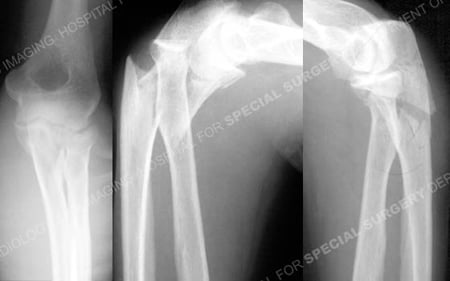

Anteroposterior, and lateral injury radiographs of the right-sided Monteggia fracture-dislocation and

lateral radiograph of the left-sided Monteggia fracture-dislocation; respectively.